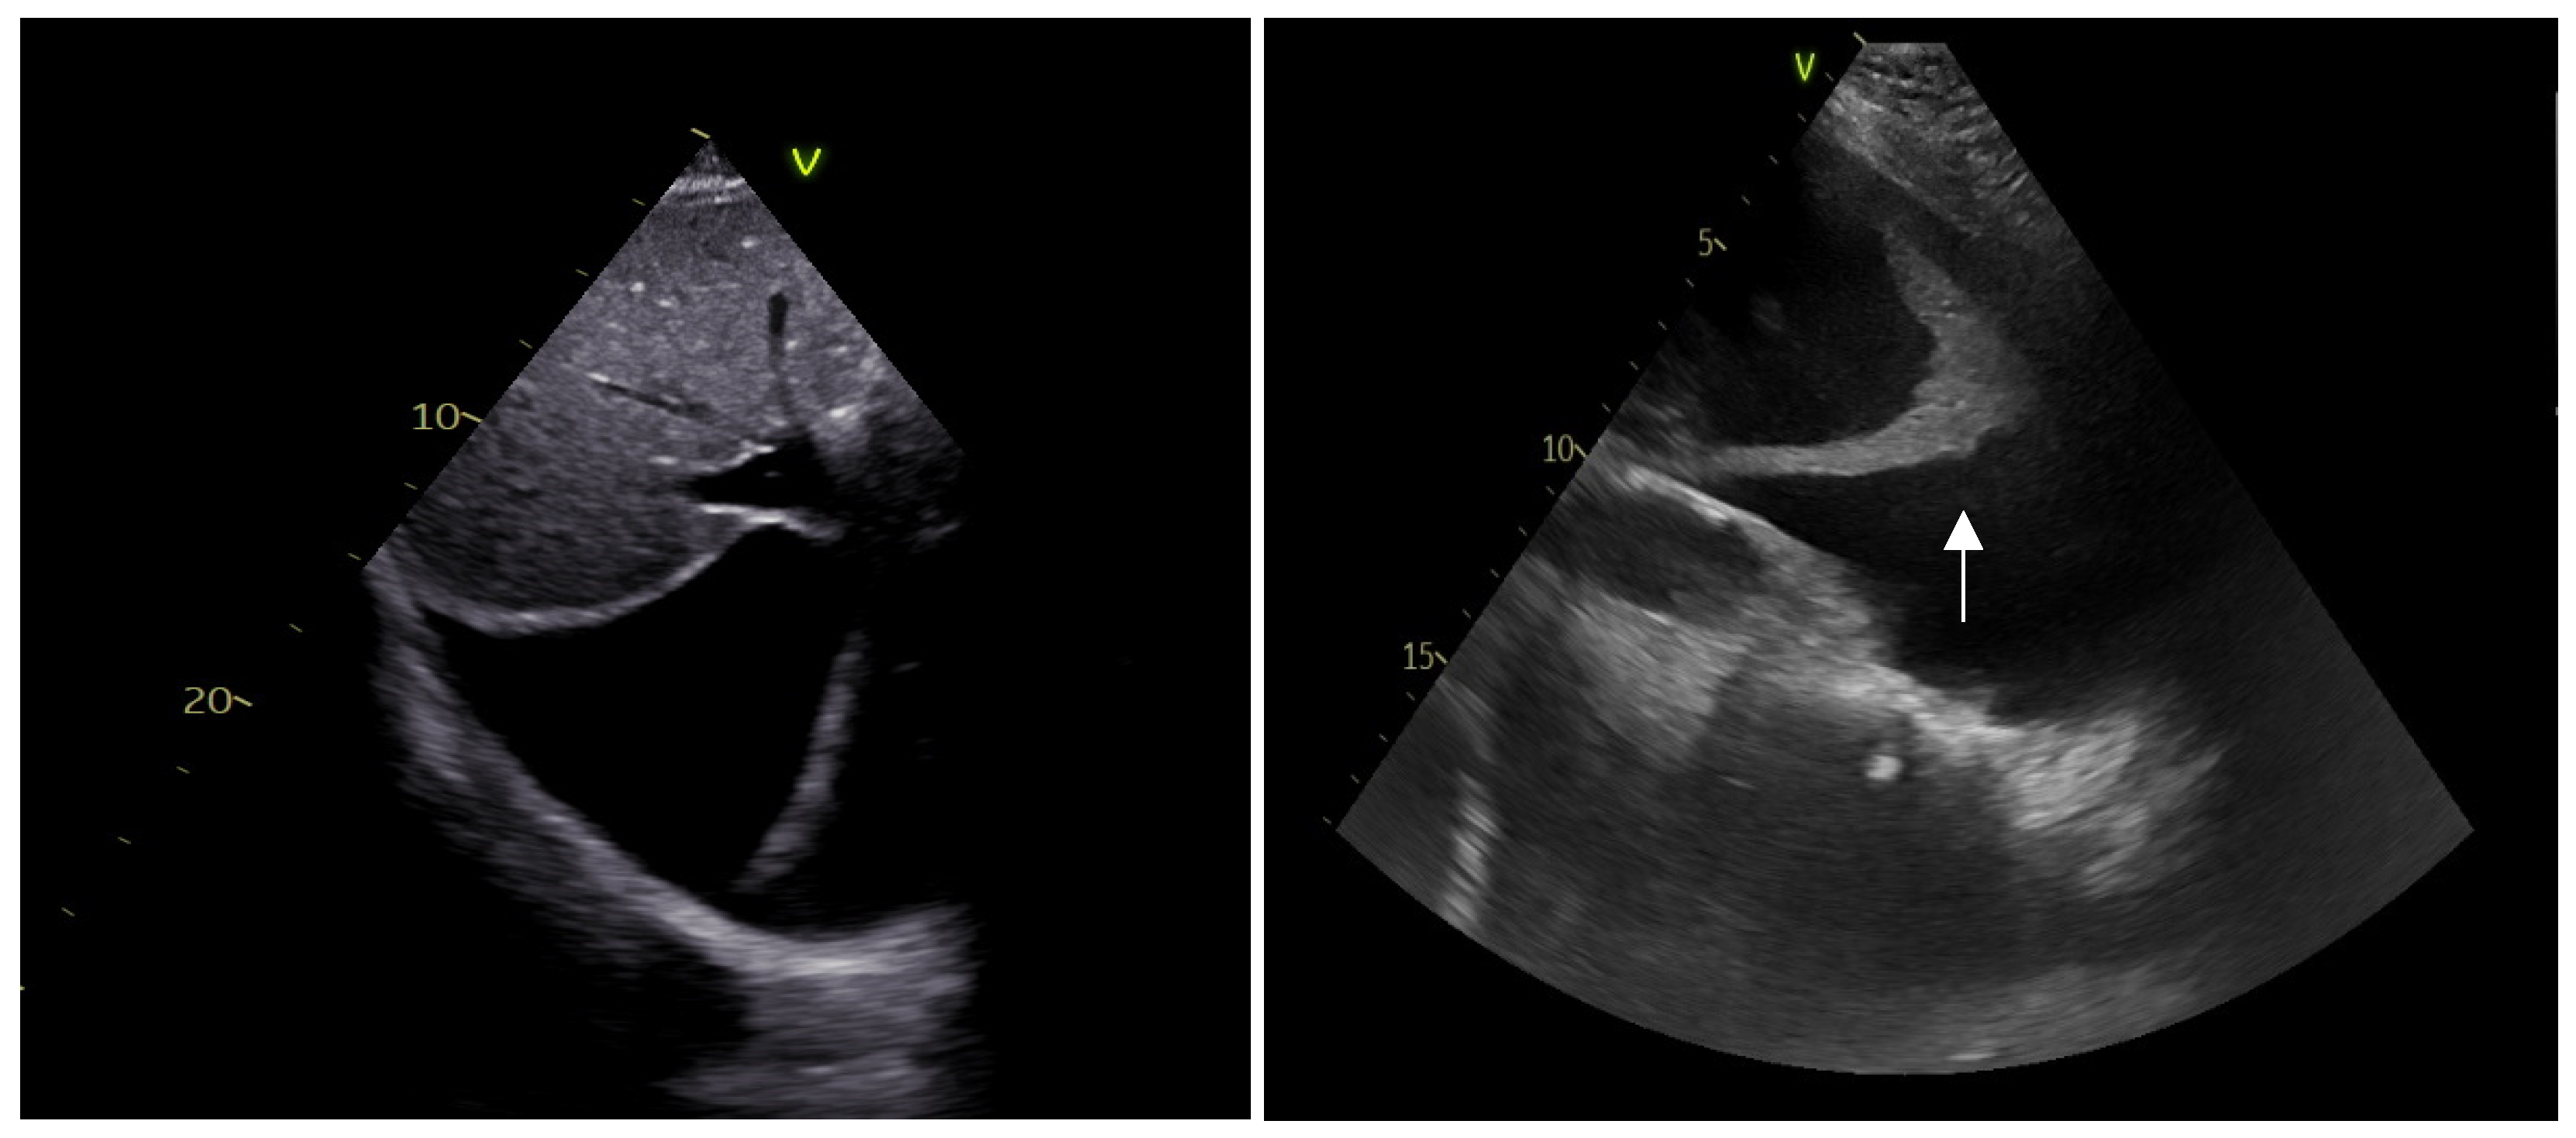

3. Cardiac Ultrasounds in the Emergency Department

3.1. Rationale and Methodology

3.2. Shock

- (E)

- Pericardium

3.3. Cardiac Arrest